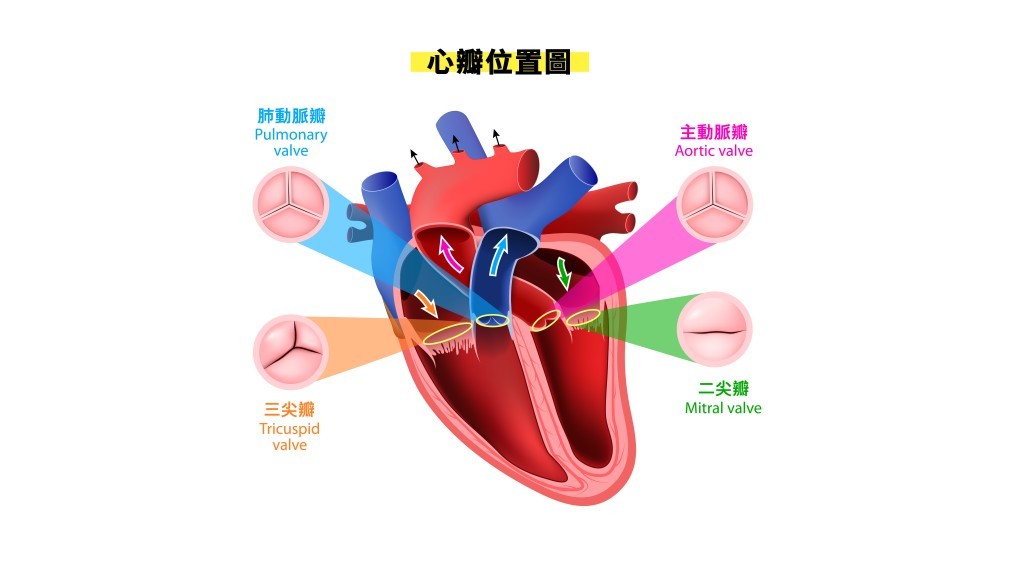

心瓣在心臟中扮演着關鍵角色,主要功能是控制血液流動,就好比一道門口。當心瓣打開時,血液可以向前流動;而當心瓣關閉時,則能防止血液倒流。心臟科專科江振昌醫生指:「簡單來說,心瓣的作用是可以確保血液只向一個方向走,不會走回頭路,令身體器官得到正常的血液供應和正常養分。正常的心臟有四塊心瓣:二尖瓣、三尖瓣、肺動脈瓣和主動脈瓣。」

正常的心臟有四塊心瓣:二尖瓣、三尖瓣、肺動脈瓣和主動脈瓣。